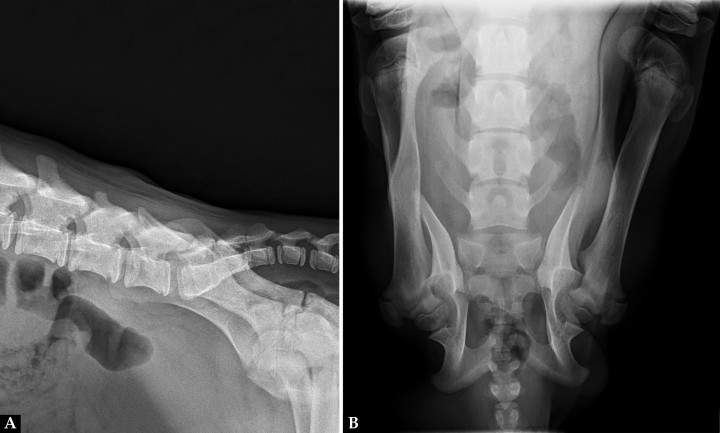

Acudió a consulta una perra mestiza de pastor alemán, entera, de 5 meses de edad y 8,6 kg de peso por paraplejia espástica sin sensibilidad nociceptiva de los miembros posteriores, estirados cranealmente, sin poder adoptar una posición natural en estación y con pérdida de orina por rebosamiento. En su casa de acogida comentaron que había nacido así. Se realizó un estudio radiográfico de la región lumbosacra, con una proyección lateral derecha y otra dorsoventral (Fig. 1).

Figura 1

(A) Radiografía lateral derecha de la región lumbosacra. (B) Radiografía dorsoventral de la región lumbosacra.

En este caso se realizó una radiografía dorsoventral en lugar de una ventrodorsal facilitada por la posición de las extremidades posteriores, rígidas de cadera a tarso y orientadas cranealmente.

En la proyección lateral (Fig. 2A) tanto la apófisis espinosa de la sexta como de la séptima vértebra lumbar tenían una altura reducida. Se observó una disminución de la radiopacidad a nivel de las apófisis articulares entre L6 y L7. El borde cutáneo a nivel de L6 era irregular y el tejido blando subcutáneo presentaba un aumento de su radiopacidad.

En la proyección dorsoventral (Fig. 2B) ambos fémures estaban posicionados en dirección craneolateral a la pared abdominal, los cóndilos rotados medialmente y las rótulas laterales a la diáfisis distal. Sobre el cuerpo y en la línea media de L6 se observaba un área radiolúcida con forma de ojo de cerradura, y no se identificaba la apófisis espinosa. La apófisis espinosa de L7 era corta y redondeada. En la línea media de la primera vértebra sacra se observaba un área radiolúcida y no se visualizaba la cresta medial sagital.